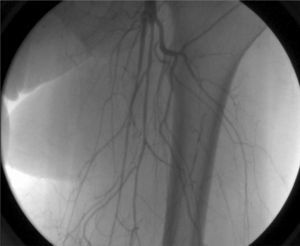

Al ultrasonido se observó reducción crítica de la perfusión, vasoconstricción generalizada por debajo de la línea inguinal con reducción del flujo femoral, sin flujo en las arterias tibiales. La arteriografía confirmó la presencia de espasmo vascular difuso bilateral manifestado como arterias filiformes sin signos de circulación colateral ni oclusión arterial segmentaria (fig. 1).

El vasoespasmo grave demostrado por ecodoppler arterial y la falta de placas ateroscleróticas nos hacen sospechar del ergotismo o vasculitis15,16. A pesar de que algunos autores no consideran el uso adicional de la angiografía16, parece ser de gran valor cuando hay duda durante el estadio clínico agudo11,14,17. Nosotros consideramos que la arteriografía confirma la estenosis vasoespástica y la oclusión, y descarta cualquier enfermedad asociada. Los signos angiográficos típicos del ergotismo vascular fueron establecidos por Bagby y Cooper en 1972 e incluyen: lesiones simétricas, circulación colateral escasa, lleno prolongado de los vasos debido al flujo sanguíneo lento, estrechamiento espástico de los vasos, imágenes en punta de lápiz, ausencia de lesión endotelial orgánica y menor espasmo en las ramas secundarias que en las principales18.